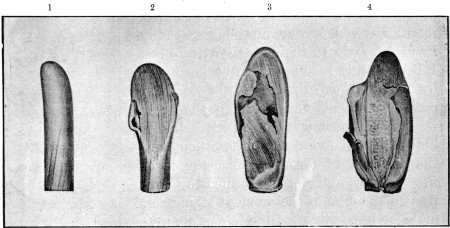

28. Four Mauser Ricochets 84

29. Mauser Ricochet, Disc Form 85

30. Fissured Mauser Mantle 86

31. Mausers Deformed by Impact on Femur 86

32. Apical Mauser Ricochet 87

33. Spiral Ricochet88